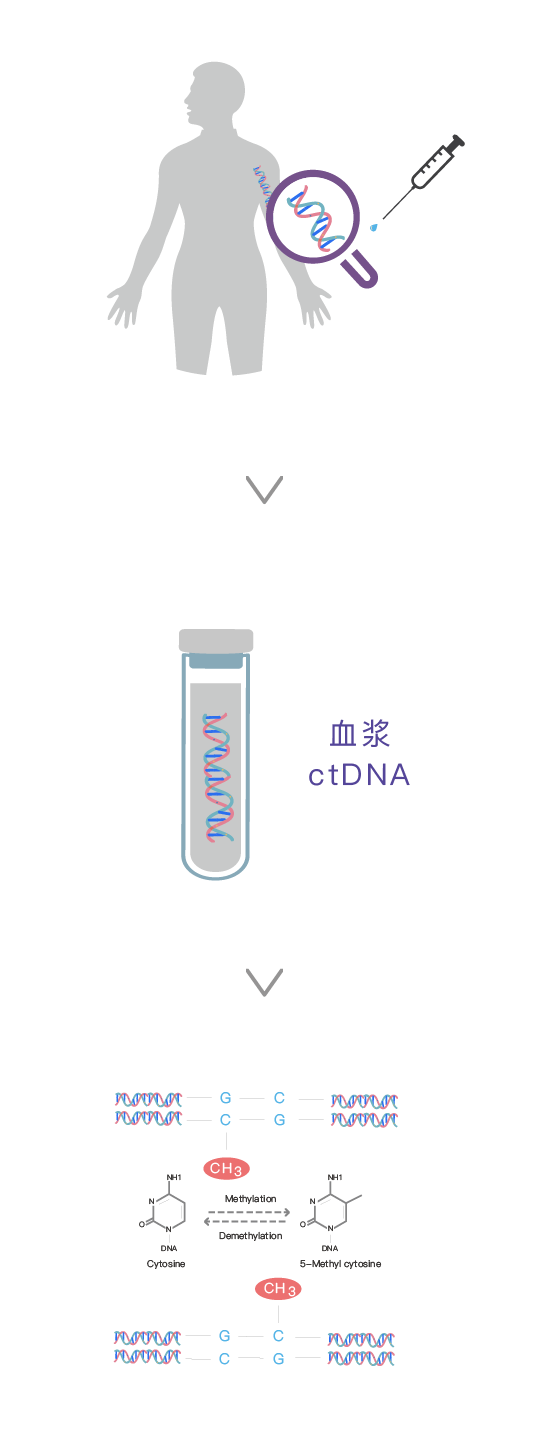

What is DNA methylation?

DNA methylation is a major epigenetic modification, and changes in the methylation pattern play a crucial role in the development of tumors. Since DNA methylation occurs almost throughout the entire process of tumor development, including precancerous lesions, it may be an ideal biomarker for early cancer diagnosis. In many types of lung cancer samples, various abnormal promoter methylation of genes have been evaluated as biomarkers.[1]

After the tumor cells carrying genetic information and epigenetic alterations undergo necrosis or apoptosis, they release fragmented genomic DNA into the peripheral blood, which is known as circulating tumor DNA (ctDNA).[2]By capturing these trace amounts of ctDNA and detecting the specific changes in tumor methylation sites, this method can provide earlier and more accurate information on the occurrence and development of tumors compared to traditional detection techniques.[3]